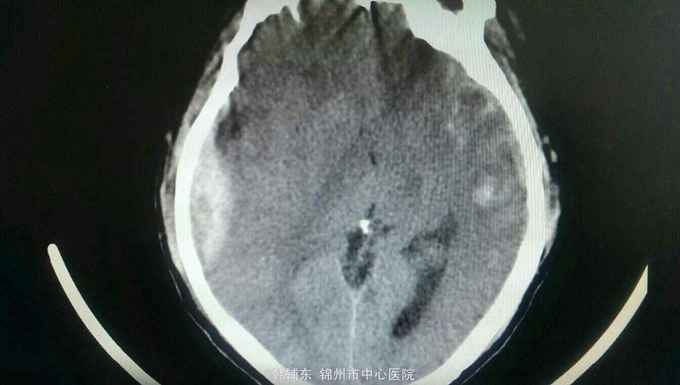

患者以车祸致头部外伤后意识不清两个小时为主诉入院。患者于入院两个小时前被汽车撞倒,伤及头部。伤后患者意识不清,恶心并呕吐数次,伤后无四肢抽搐。急诊以硬膜外血肿收入院。

中度昏迷状态,无语言,刺激后右侧肢体可动,左侧肢体不动。右颞头皮肿胀,双侧瞳孔不等大,右侧瞳孔直径5.0毫米,光反射无,左侧瞳孔直径3.0毫米,光反射迟钝。颈软,左侧肢体不动,右侧肢体少动。左侧病理反射阳性。头部ct如下。

诊断:脑疝 急性硬膜外血肿 脑挫裂伤 颅骨骨折 入院后完善术前准备,急诊行去骨瓣硬膜外血肿清除术。术中见骨折线,清除血肿,悬吊硬膜。术后复查ct提示对侧脑挫裂伤增大,伴水肿,暂不需要手术。降颅压治疗,密切观察病情变化。